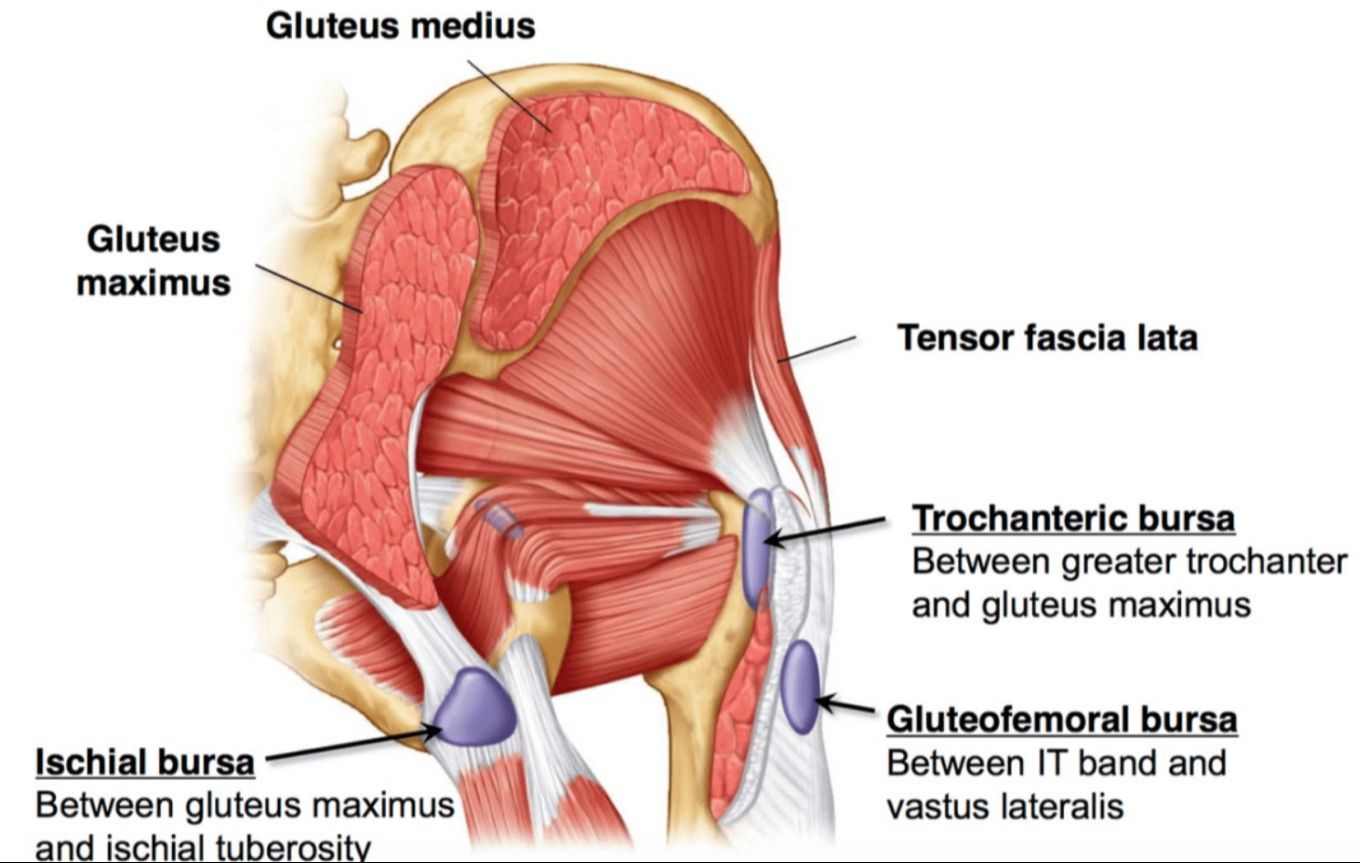

The greater trochanter is a common area of bursitis. As you can see in the diagram, it's a central location for muscles and connective tissue to connect. The Iliotibial band (IT band) is of great importance. You have to consider why the bursitis began in the first place and it usually has to do with the functionality of the surrounding tissues.

Bursitis occurs when the small, fluid-filled sacs called bursae, which cushion the bones, tendons, and muscles around your joints, become inflamed. This can lead to pain, swelling, and difficulty moving the affected area.

As you can see the bursa sack lies between the greater trochanter bone and the gluteus maximus muscle. The IT band runs over the top of this area stabilizing the knees and hips.